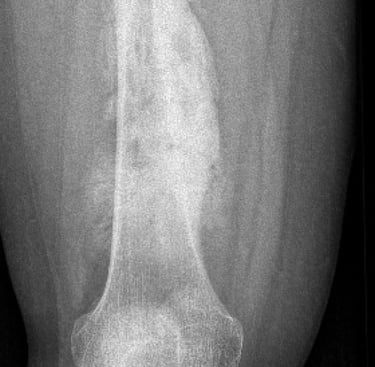

Osteosarcoma is the most common between the ages of 10 to 30 and those > 60 years old. There is no known cause in majority of patients but certain factors are known to increase your risk eg. previous radiotherapy, paget's disease, fibrous dysplasia, bone infarcts or Li Fraumeni syndrome. Most occur around the knee but can occur in any bone. Treatment generally involves combination of chemotherapy and surgery.

Diagnosis of this is generally made with Xrays, CT, MRI, PET scans and a core needle biopsy.